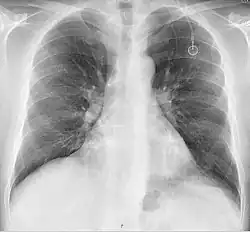

The port is usually inserted in the upper chest (known as a "chest port"), just below the clavicle or collar bone, with the catheter inserted into the jugular vein.

A port consists of a reservoir compartment (the portal) that has a silicone bubble for needle insertion (the septum), with an attached plastic tube (the catheter). The device is surgically inserted under the skin in the upper chest or in the arm and appears as a bump under the skin. It requires no special maintenance other than occasional flushing to keep clear. It is completely internal so swimming and bathing are not a problem. The catheter runs from the portal and is surgically inserted into a vein (usually the jugular vein or less optimally the subclavian vein). Ideally, the catheter terminates in the superior vena cava or the right atrium. This position allows infused agents to be spread throughout the body quickly and efficiently.

The port is then sutured on two sites to the underlying muscles. The tip of the catheter is checked for kinks and position using a fluoroscope. Besides that, aspiration of blood and contrast injection through the chemoport can also be used to confirm the position. The port is the closed in two layers (subcutaneous tissue is sutured first, followed by the skin). Sterile dressing is then placed on the port.[3] The optimum site to park the tip of the catheter is at the cavo-atrial junction or with margin of error of not more than 4 cm above the junction.[3]

A follow-up on a chest radiograph can immediately detect complications associated with the procedure such as pneumothorax, hemothorax and malpositions of the catheter. However, routine chest radiography is not needed due to the low complication rates associated with the procedure. The chest radiograph is only done if there is clinical suspicion of a complication.[4]

Ports can be put in the upper chest or arm. The exact positioning itself is variable as it can be inserted to avoid visibility when wearing low cut shirts, and to avoid excess contact due to a backpack or bra strap. The most common placement is on the upper right portion of the chest, with the catheter itself looping through the right jugular vein, and down towards the patient's heart.